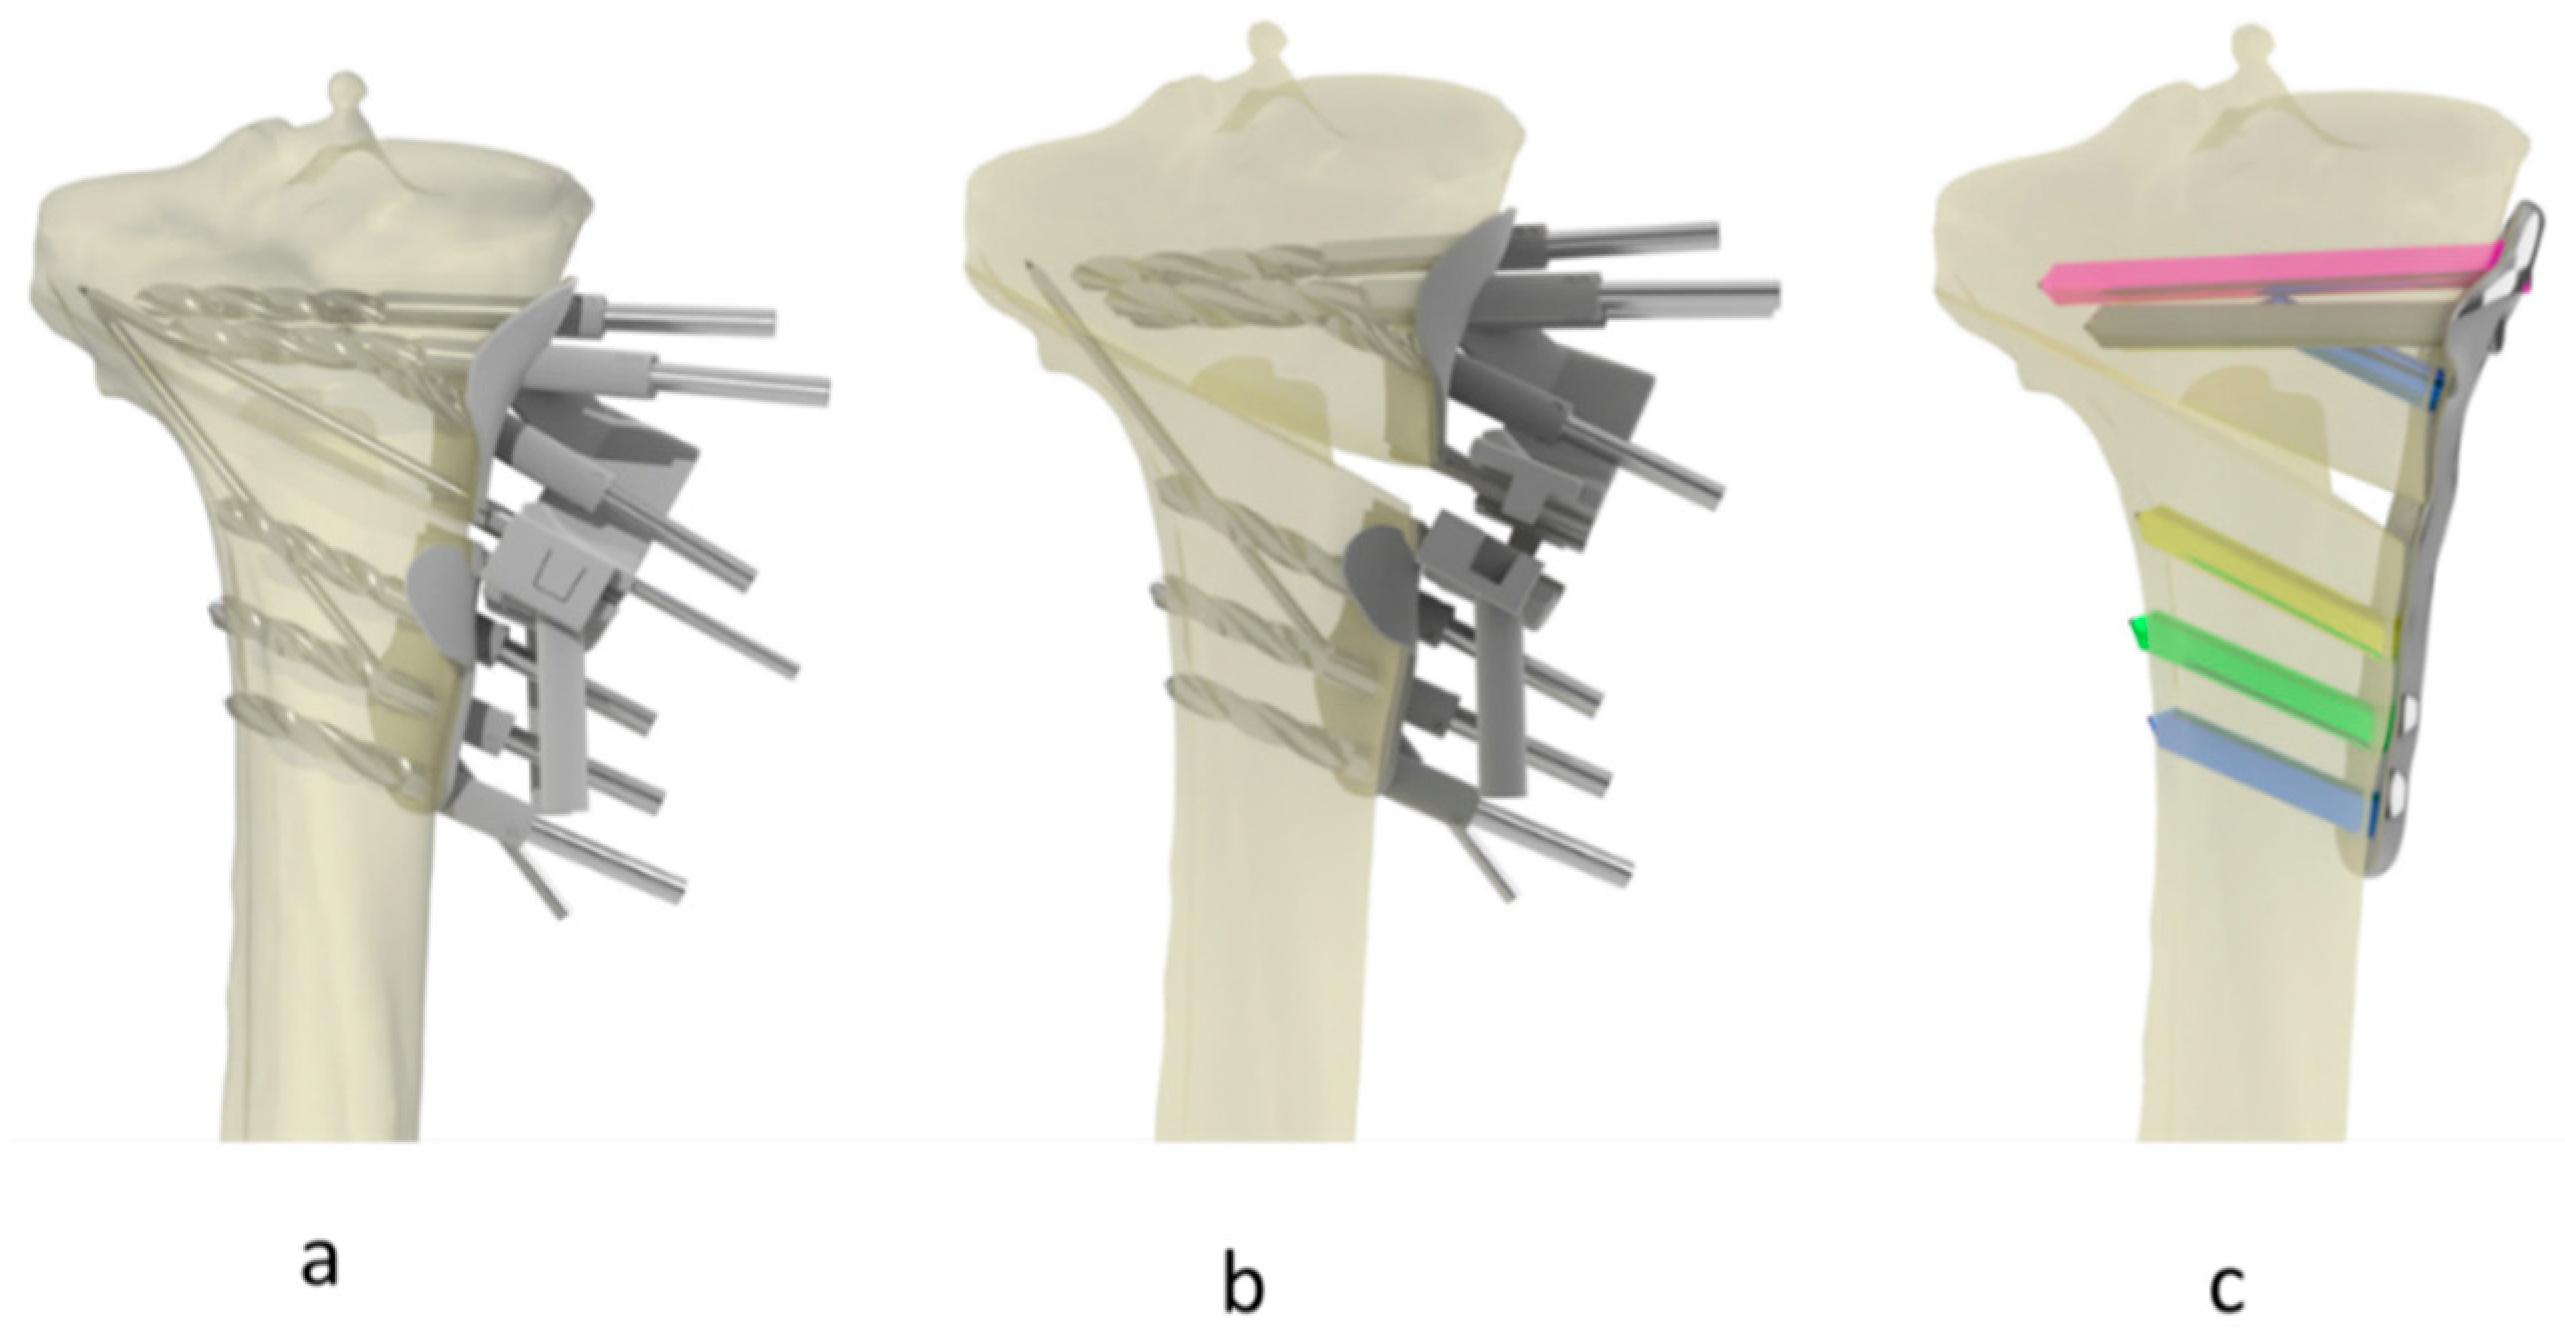

2.3. Imaging, Surgical Planning and Procedure